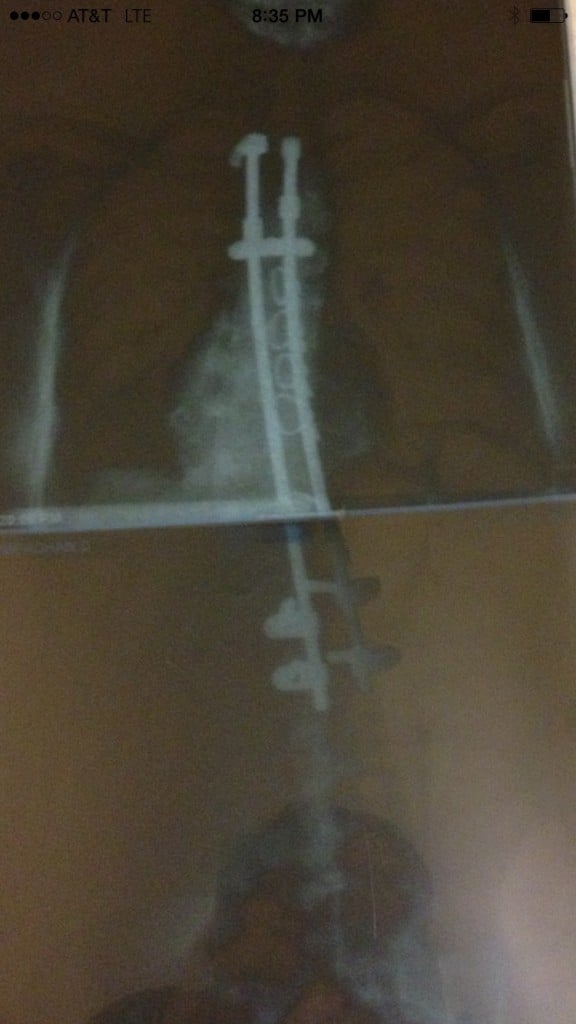

My story began when I was entering 5th grade. After the very standard scoliosis screening, I was referred to a specialist since my spine had concerning curves. As the degree of the curves progressed, I was fitted for the Boston Brace. As if the experience of middle school wasn't already awkward enough, I had to wear the brace for 23 hours a day for three years. Over the course of these three years, my curves continued to progress. Not only did my spine curve, but it was also twisting, which had the potential for some serious complications. By the time I was a freshman in high school, doctors recommended spinal fusion surgery. This was scary, very scary. Not only for me, but for my family as well. There was no one in the world who could convince my mom that her youngest daughter would be better off with a major operation leading to titanium rods and pedicel screws in her back, no one except the comforting and knowledgeable Dr. Bernard Rawlins from the Hospital for Special Surgery.

I strive to stay as healthy and active as possible. To me, it is the least I can do after being given a second chance at a healthy body. Looking at your own x-rays of 70 degree curves and being told your lung capacity will soon be affected makes scoliosis scary. HSS provided me an opportunity to exchange those x-rays for straighter ones and for that, I am eternally grateful. Although I am just one of Dr. Rawlin's thousands of patients, he will always be my number one doctor. I am thankful to him for his medical expertise, support to my family, and calming personality. He is a remarkable man who does so much for many people. He has donated a great deal of his time and resources to his home country of Ghana, so that the children their can also live happy and healthy lives. If we could all strive to adopt his giving personality, this world would be a better place! Thank you Dr. Rawlins and HSS!